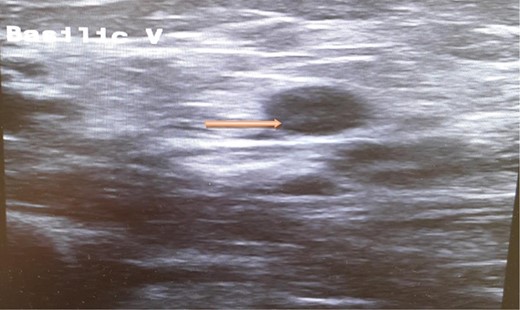

A computed tomography scan of the chest, abdomen and pelvis revealed splenic vein thrombosis (Fig. 1); and a filling defect in the lower lobar segmental branch of the right pulmonary artery consistent with acute segmental pulmonary embolism. A venous duplex scan of the extremities showed thrombosis of the left axillary and basilic veins (Figs 2 and 3). Echocardiogram was normal.

Ultrasound scan of the basilic vein with evidence of thrombus formation.